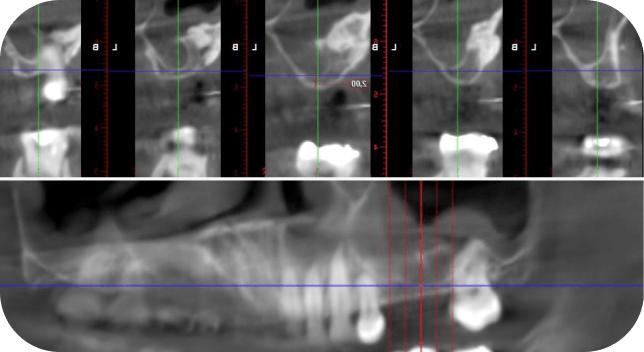

Узнаете, как проводить повторный синус-лифтинг с минимальным риском разрыва Шнейдовской мембраны и других осложнений.

Ре-синус. Протокол работы